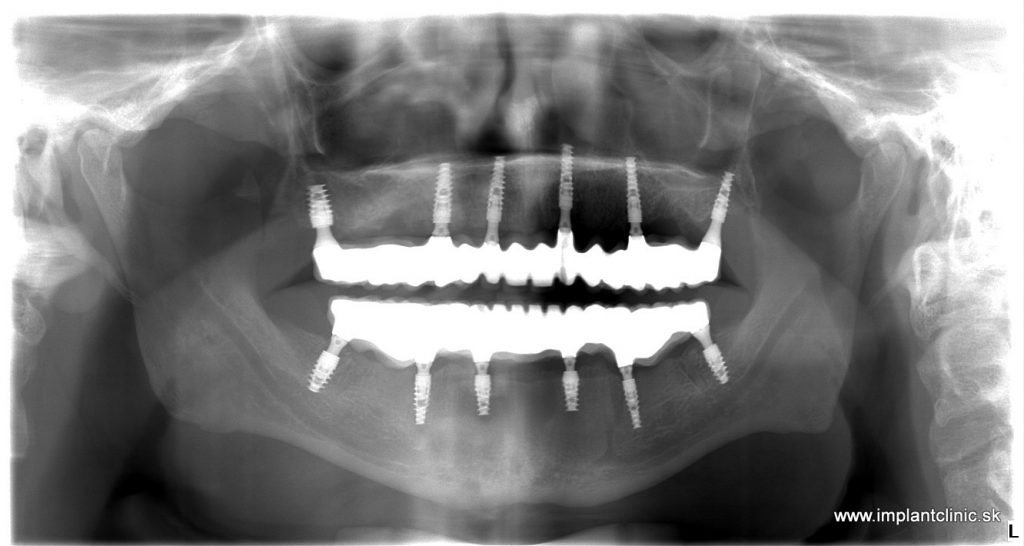

Tento pán prišiel s narušenou žuvacou funkciou. Po konzultácii s implantológom sme navrhli plán: zaviedli sme 6 zubných implantátov a nasadili 14-členný mostík do oboch čeľustí. Ošetrenie sme rozdelili na dve sedenia, aby sme zabezpečili pohodlie a plynulý priebeh.